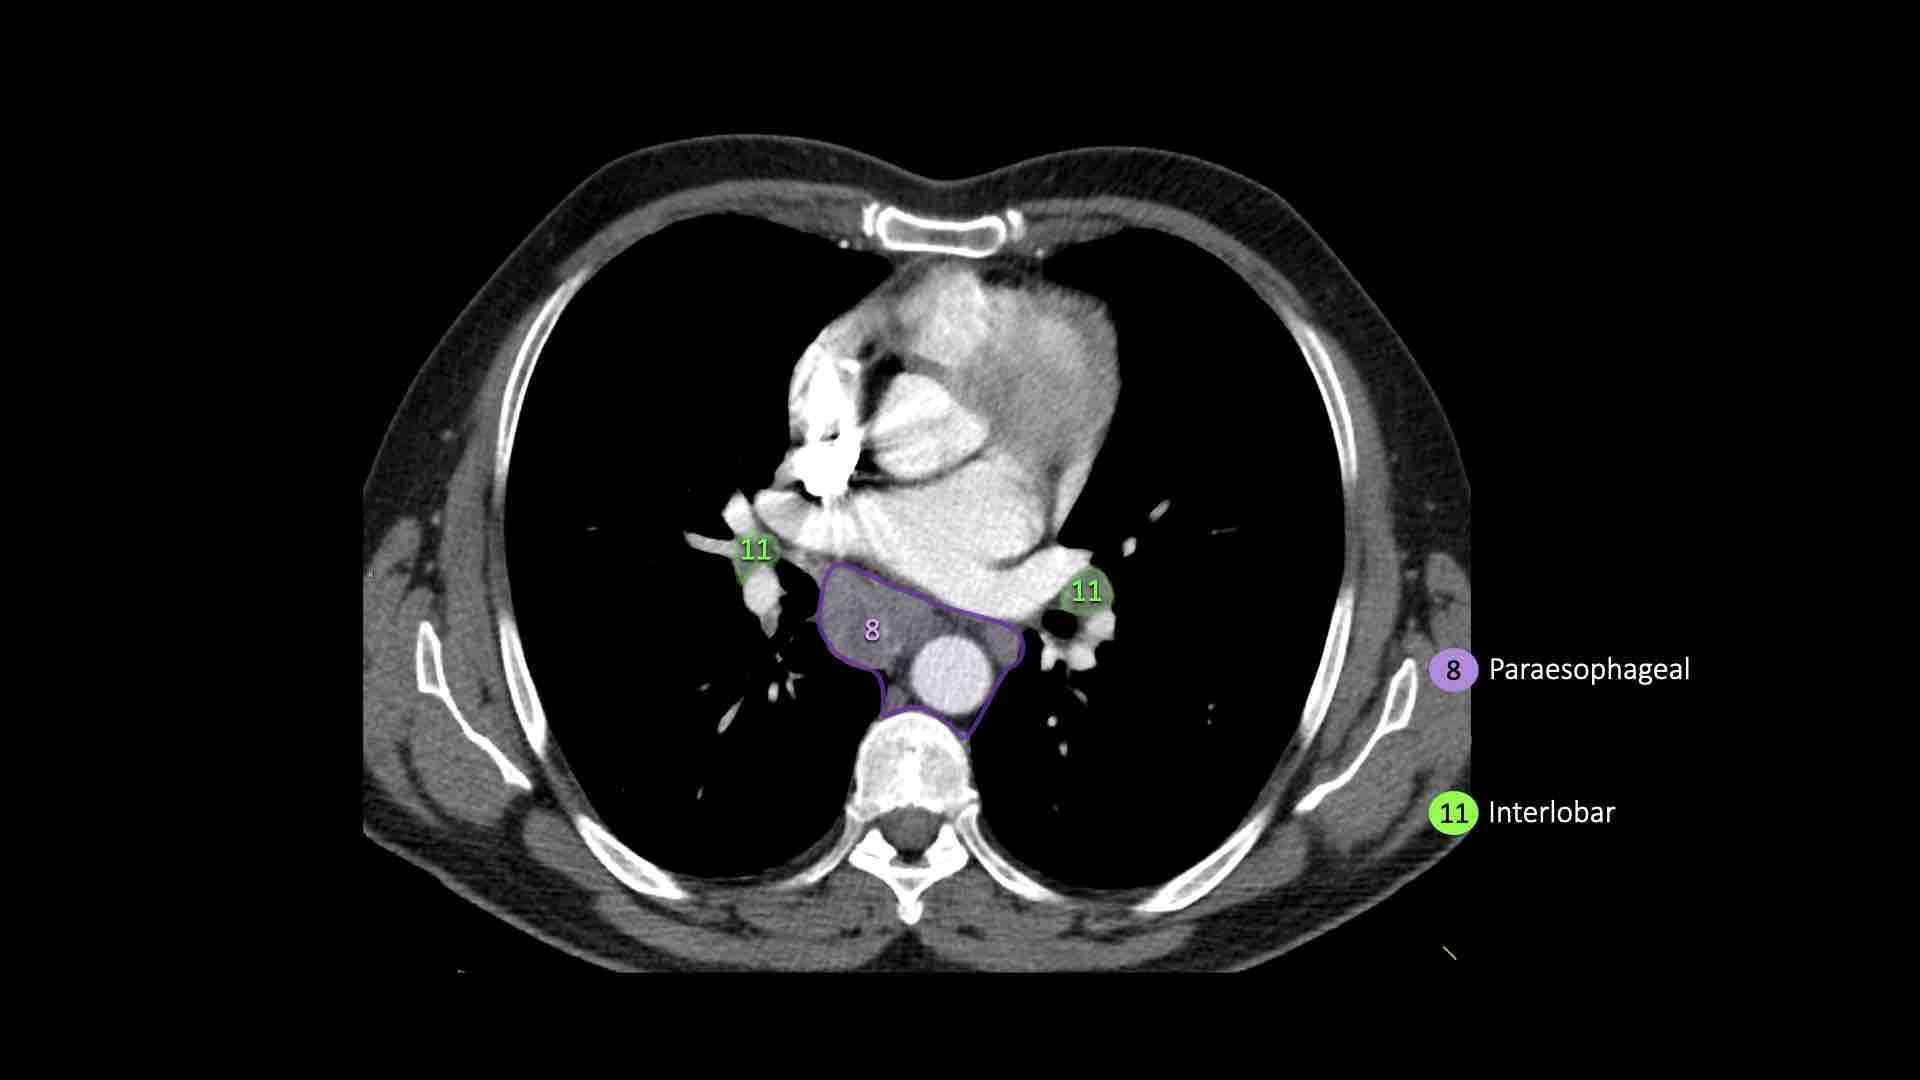

8. Hạch cạnh thực quản

Các hạch này nằm bên dưới các hạch dưới carina và trải dài xuống đến cơ hoành.

Bên trái là hình ảnh dưới mức carina.

Bên phải thực quản là một hạch nhóm 8.